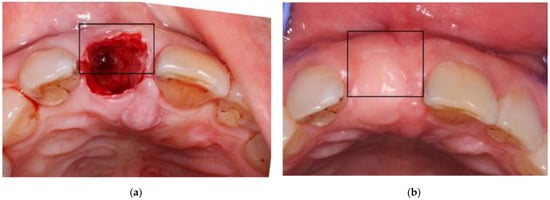

2.4. Measurements of the Alveolar Ridge Contour Changes

T0 images (taken immediately after extraction) and T6 images (taken after 6 months of healing) were imported into the PowerPoint software (Microsoft corp., Redmond, Washington, WA, USA). A rectangle, the width of which corresponds to the edentulous gap, was superimposed on the T0 photograph, which was rotated until the rectangle was perpendicular to a line connecting the mid bucco-lingual point on the 2 neighboring teeth (Figure 1a). The upper border of the rectangle was moved to correspond to the most buccal edge of the extraction site. The vertical/horizontal ratio of the rectangle was registered so that the buccal dimension of the extraction site was defined as percent of the gap between the neighboring teeth. The rectangle was copied onto the T6 photograph, which was adapted to it while keeping the vertical-to-horizontal proportions intact and the same procedure was repeated (Figure 1b). With this technique, the dimensions of the 2 photographs were equalized before measurements were made. Notably, the measurements reflected only the outer contour of the alveolar socket, without separating the bony and soft tissue components. The buccal width of the site of the T6 photograph was multiplied by 100 and divided by that of the T0 photograph. Consequently, a value greater than 100 means that the site gained buccal width at 6 months and a value less than 100 means that its buccal dimensions diminished.

Figure 1. T0 (a) and T6 (b) images with a superimposed vertical rectangle which borders the most buccal edge of the edentulous gap.